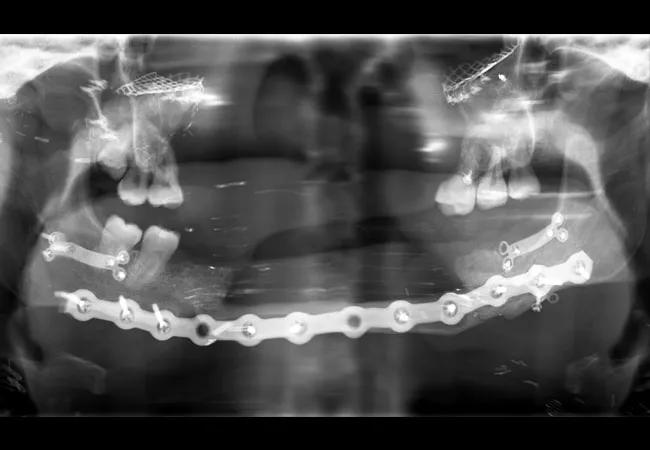

Shortly after arriving at the Cleveland Clinic, Katie began to localize pain to several teeth. Given her condition, obtaining intraoral radiographs proved difficult; to make matters worse, the images were compromised by shadowing of hardware (Figure 1; see large image above). Early on, a decision was made to maintain as many teeth as possible to allow for retention of any future maxillofacial prosthesis. Her maxillary teeth were treated if they were symptomatic, with the understanding that they would be replaced with the transplant. Restoration of teeth was attempted before any extractions were considered. Oral Surgery performed extractions of any infected or non-restorable teeth in the time leading up to the facial transplant (Figure 2). When her transplant was eventually performed, Katie received both the donor’s maxilla and mandible. At the time of the surgery, all of her remaining teeth were removed and she was essentially provided with an entirely new dentition (Figure 3).

Oral Surgery performed extractions of any infected or non-restorable teeth in the time leading up to the facial transplant

Figure 2